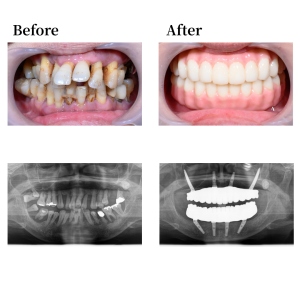

上顎骨の形状を整え、12,22の位置にノーマルインプラントを0度垂直埋入。15, 25 の位置にザイゴマインプラントを30度傾斜埋入。下顎も形状を整え、45, 42, 32, 35の位置にそれぞれオールオン4インプラントを埋入。 42, 32の位置に、0度垂直埋入、45, 35の位置に30度傾斜埋入。その後、マルチユニットアバットメントで角度補正を行い、プロビジョナルレストレーション(審美的な仮歯)を装着した。

上下顎はUTジルコニアで構成された、フルジルコニアブリッジでファイナルレストレーションとした。焼成されたジルコニアはステインテクニックで着色した。シェードカラーはA1。